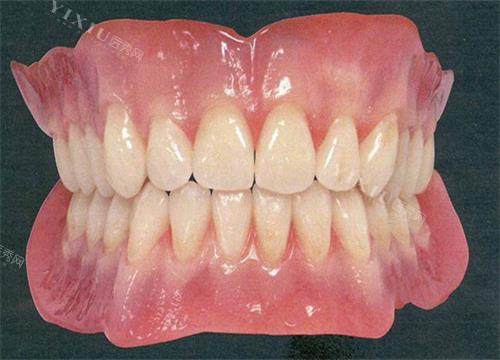

牙冠颜色定制得和真牙一样,老伴说“像年轻了十岁”。

定期复查时,医生总说:“您这牙比我预想的结合得还好!”